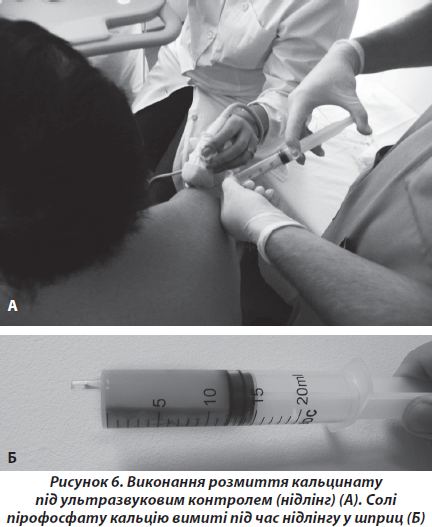

Під час ультразвукового дослідження плеча у хворих відмічалось гіперехогенне вогнище, локалізоване в товщі сухожилка надостного мяза. Таким хворим ми встановлювали діагноз кальціфікуючого тендиніту сухожилка надостного м’яза. Відомо, що в ділянці прикріплення сухожилка надостного м’яза до плечової кістки існує зона критичного кровообігу. Саме в цьому місці найчастіше винкає некроз сухожилка з подальшим заміщенням некротизованого сухожилка пірофосфатом кальцію [10]. При локалізації кальцінату в товщі сухожилка надостного м’яза виникають симптоми субакроміального конфлікту, виявлені в більшості хворих. Проте при пошкодженні покривного шару сухожилка виникає вихід речовини кальцинату в порожнину субакроміальної сумки [10]. Пірофосфат кальцію є осмотично активним, викликає різкий біль та запалення в субакроміальній сумці, чим пояснюються клінічні прояви в меншої кількості пацієнтів даної групи. Лікування хворих даної групи ми проводили двома методиками. Перша методика заснована на тому, що кальцинат не є петрифікатом, фактично це депо кристалів колоїдної речовини, що не розчиняється у воді, проте може бути механічно вимита. За допомогою ультразвукового апарату виявляли кальцинат, після місцевого знеболення поверхневого шару тканин розчином місцевого анестетика, під ультразвуковим контролем у кальцинат вводили голку для спинномозкової анестезії 16 G. До голки під’єднували шприц, наповнений фізіологічним розчином. Під час циклів послідовного нагнітання — аспірації фізіологічного розчину вимивали кальцинат (рис. 6).

Після маніпуляції проводили консервативне лікування, подібне до хворих 1-ї групи. Через 1 місяць проводили рентгенологічний та ультразвуковий контроль. Ми виявили кальцинат у 36 % хворих через 1 місяць після первинного промивання. Пояснюємо це продовженням процесу кальцифікації некротизованої частини сухожилка. У такому випадку маніпуляція повторювалась, через 1 місяць знов проводився рентгенологічний та ультразвуковий контроль. У 4 % загальної кількості хворих повторно виявили кальцинат. Таким хворим ми пропонували оперативне лікування — видалення кальцинату та видалення некротизованих частин сухожилка надостного м’яза під артроскопічним контролем. У даної групи хворих ми отримали покращення функціонального стану плечового суглоба від 43,6 до маніпуляції до 92,5 бала через 1 рік після початку лікування. Рецидивів кальцифікування ми не виявили в жодного хворого.